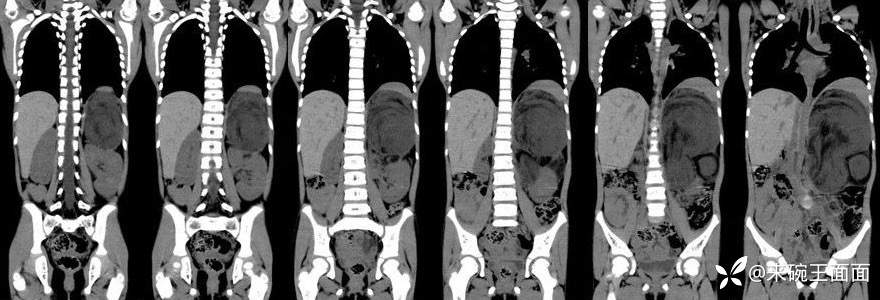

[现病史]1月余前无明显诱因发现左上腹肿物,无发热,无呕吐,无腹痛、腹泻、排便困难及其他不适,无尿频尿急,至当地医院CT示左上腹巨大占位性病变。【体格检查]腹膨隆,未及胃肠型及蠕动波,未及腹壁静脉曲张,腹软,左上腹可及大小约10*10cm肿物,质中,位置固定,无压痛、反跳痛,肝脾肋下未及,移动性浊音阴性,肠鸣音4-5次/分。

左上腹巨大软组织肿块影,密度混杂,边界清楚,其内可见脂肪密度,增强扫描未见强化。